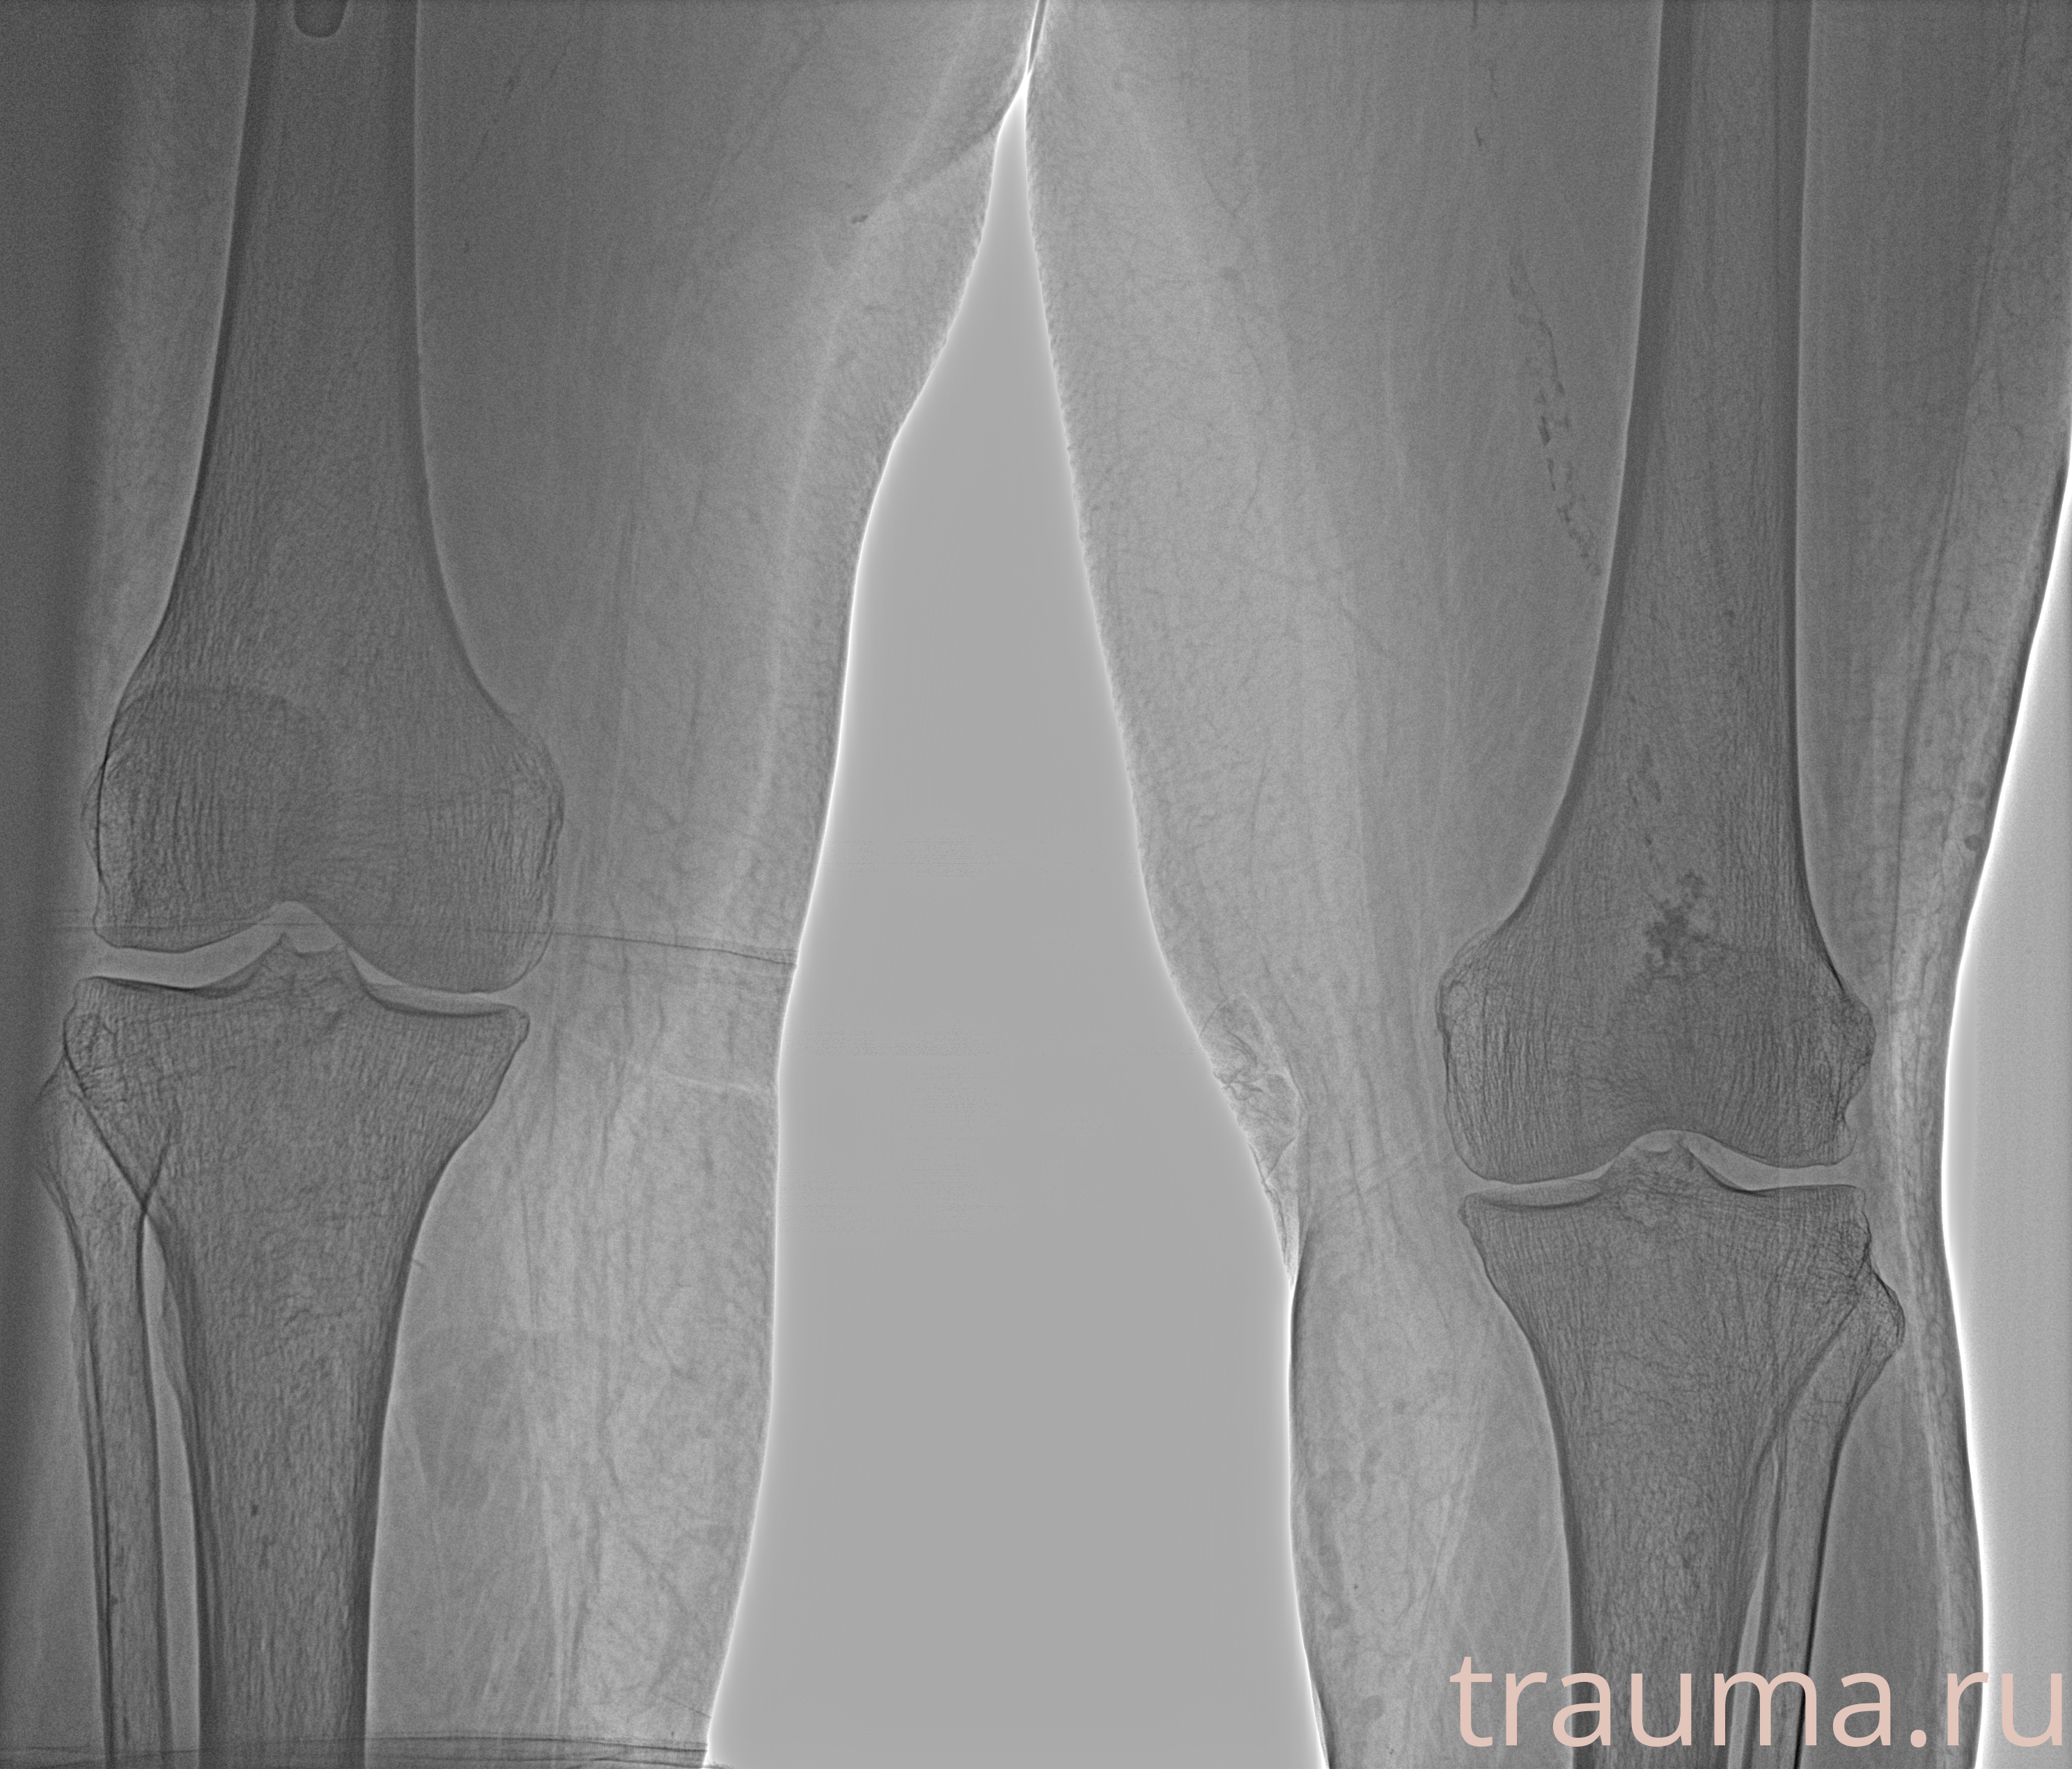

Рентгенограммы

Рентген на дому: по вашему адресу приезжает врач-рентгенолог, травматолог-ортопед с мобильным рентгеновским аппаратом, проводит диагностику травмы или заболевания, делает необходимые рентгенограммы, дает рекомендации по дальнейшему лечению. Получить качественные снимки в домашних условиях возможно благодаря уникальной методике, разработанной МосРентген Центром для института  Склифосовского